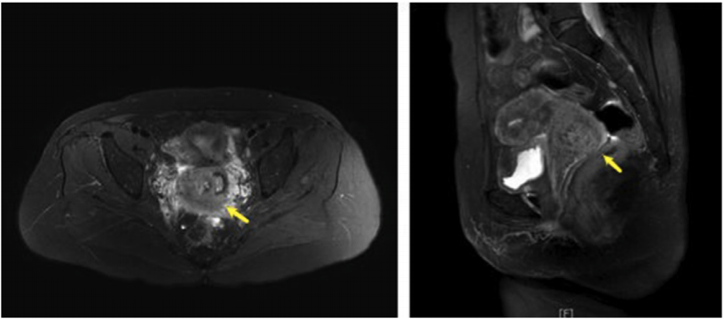

盆腔3T磁共振成像(MRI)显示子宫颈右侧有3.7×3.6×4.0 cm坏死肿块,周围增强。在左侧髂外动脉后方的左侧盆腔内发现一个直径为1.8cm的肿大淋巴结(图1)。

图1. 盆腔3T MRI显示一个3.7×3.6×4.0cm的坏死肿块,在T2加权图像上内部信号不均匀